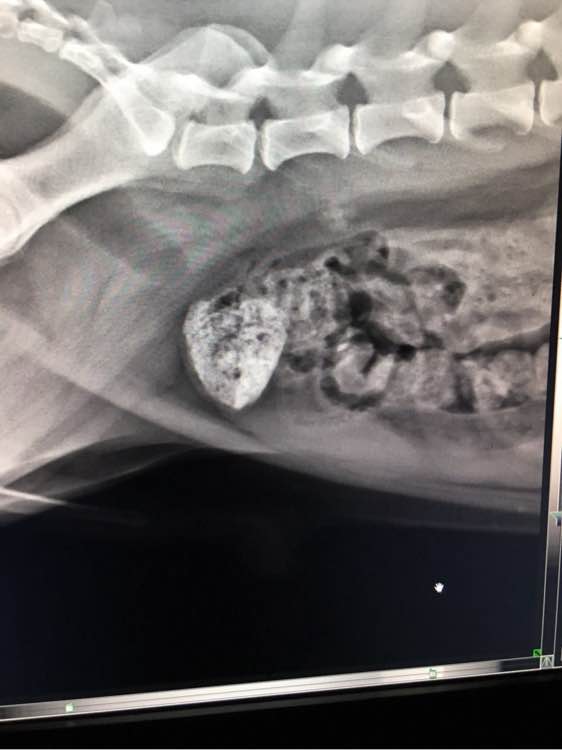

有看的懂的嘛?两岁泰迪,很灵活,一直想拉拉不出来,拍片如图